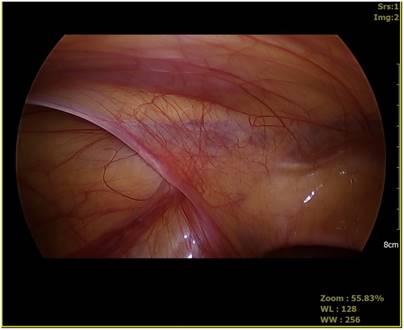

Fig 1

Laparoscopic view of hernia site.

Patients underwent surgery with pelvis slightly elevated in supine position. A 5 mm, 30° angled laparoscope was inserted above or through the umbilicus. We maintained an 8mmHg pressure for pneumoperitoneum, confirmed unilateral hernia, and evaluated contralateral side processus vaginalis opening. Two 2.7 mm laparoscopic needle holders were inserted into both abdominal sides at the level of umbilicus. The internal opening of inguinal hernia was then ligated using a purse string suture method. In the case of the opposite-side PPV, it was sutured using the same method (Fig. 1, Fig. 2). Contralateral PPV repair indication was: depth of PPV > 1 cm, no relation with diameter of PPV or shape.

There are two methods to observe the contralateral side internal inguinal area: laparoscopic examination through the inguinal hernia sac and laparoscopic examination through the umbilicus. Laparoscopic examination through the hernia sac is more commonly applied after it was first reported by Lobe et al. [20]. Sozubir et al. [8] have performed laparoscopic inguinal internal ring examination through hernia sac in 497 patients and reported that the rate of opening is 19.4% with positive predictive value of 100%. However, 6 patients did not undergo laparoscopic examination due to anatomical problems [8]. Laparoscopic inguinal examination through hernia sac cannot be performed when the hernia sac is too weak. In some cases, the peritoneal veil can result in false negative finding (Fig. 3). The failure rate of laparoscopic inguinal examination through hernia sac due to peritoneal veil is 3-8% [21].

Fig 3

Peritoneal veil.